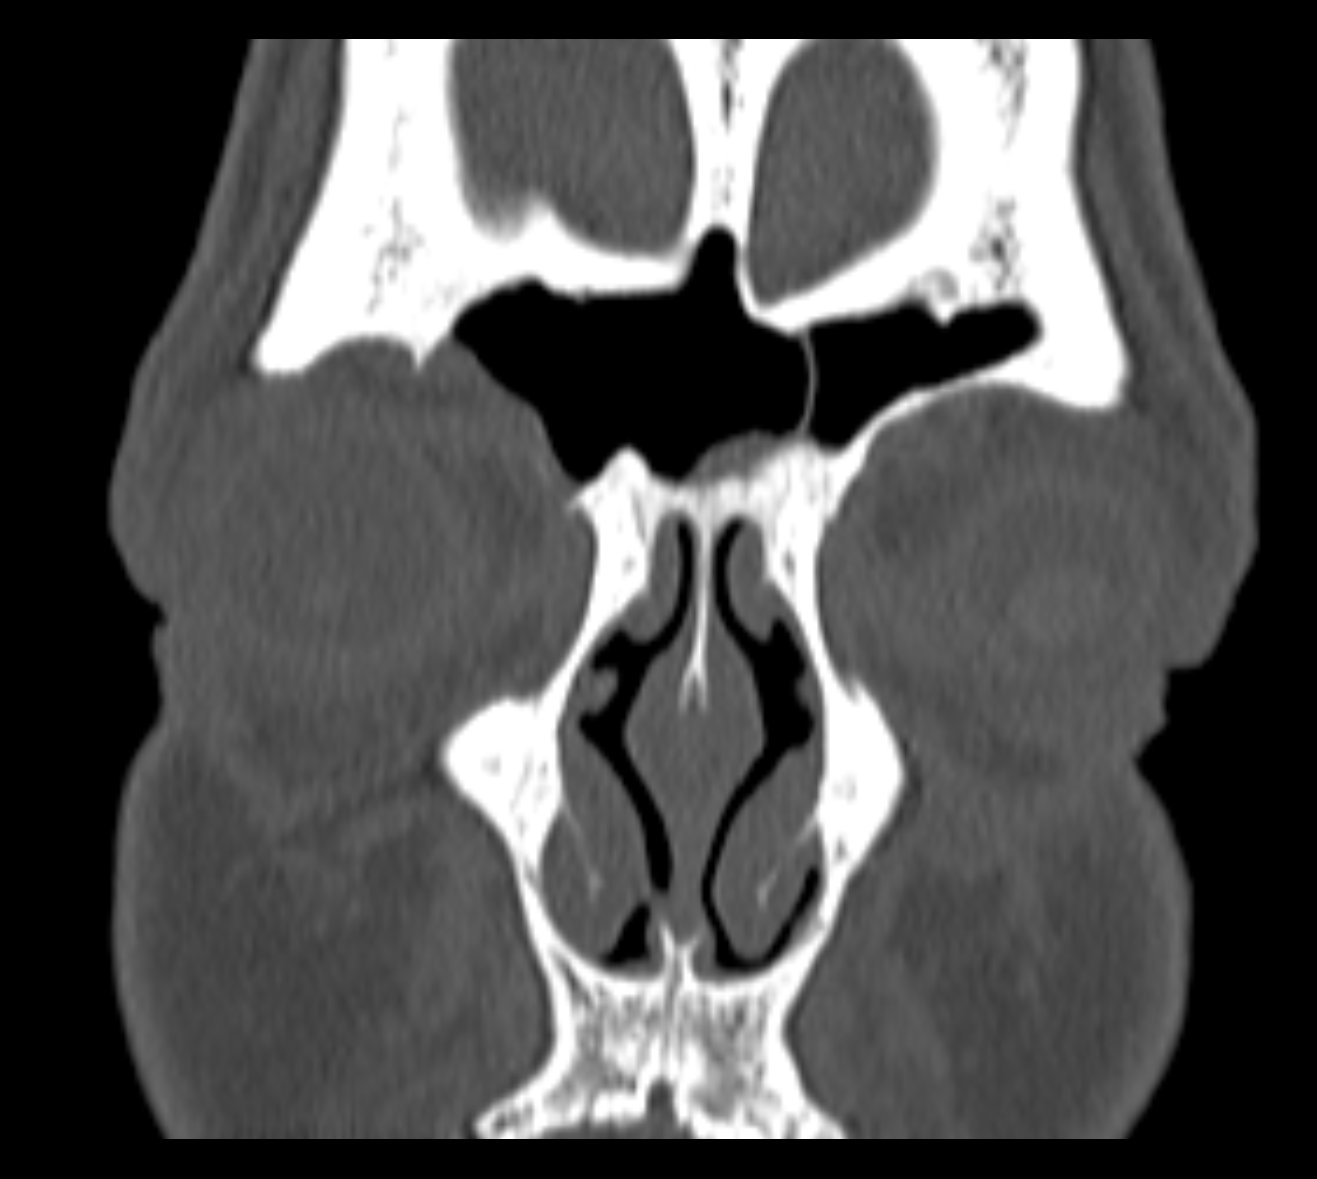

Examenul clinic ORL și examenele imagistice complementare (CT, RMN sinusuri paranazale) pun în evidență o formațiune tumorală osteogenică a sinusului frontal drept, protruzivă în unghiul supero-intern al orbitei, extinsă medial către sinusul frontal stâng.